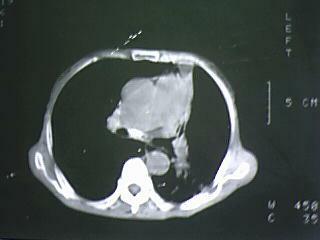

以下是引用xiaomeng在2009-5-4 16:46:00的发言:[br]肺癌

以下是引用杀毒软件在2009-5-4 17:57:00的发言:[br]块影+不张=肺癌

以下是引用随光逐影在2009-5-4 19:15:00的发言:[br]1)考虑左肺周围型肺癌。2)左肺感染性病变并节段性肺不张。